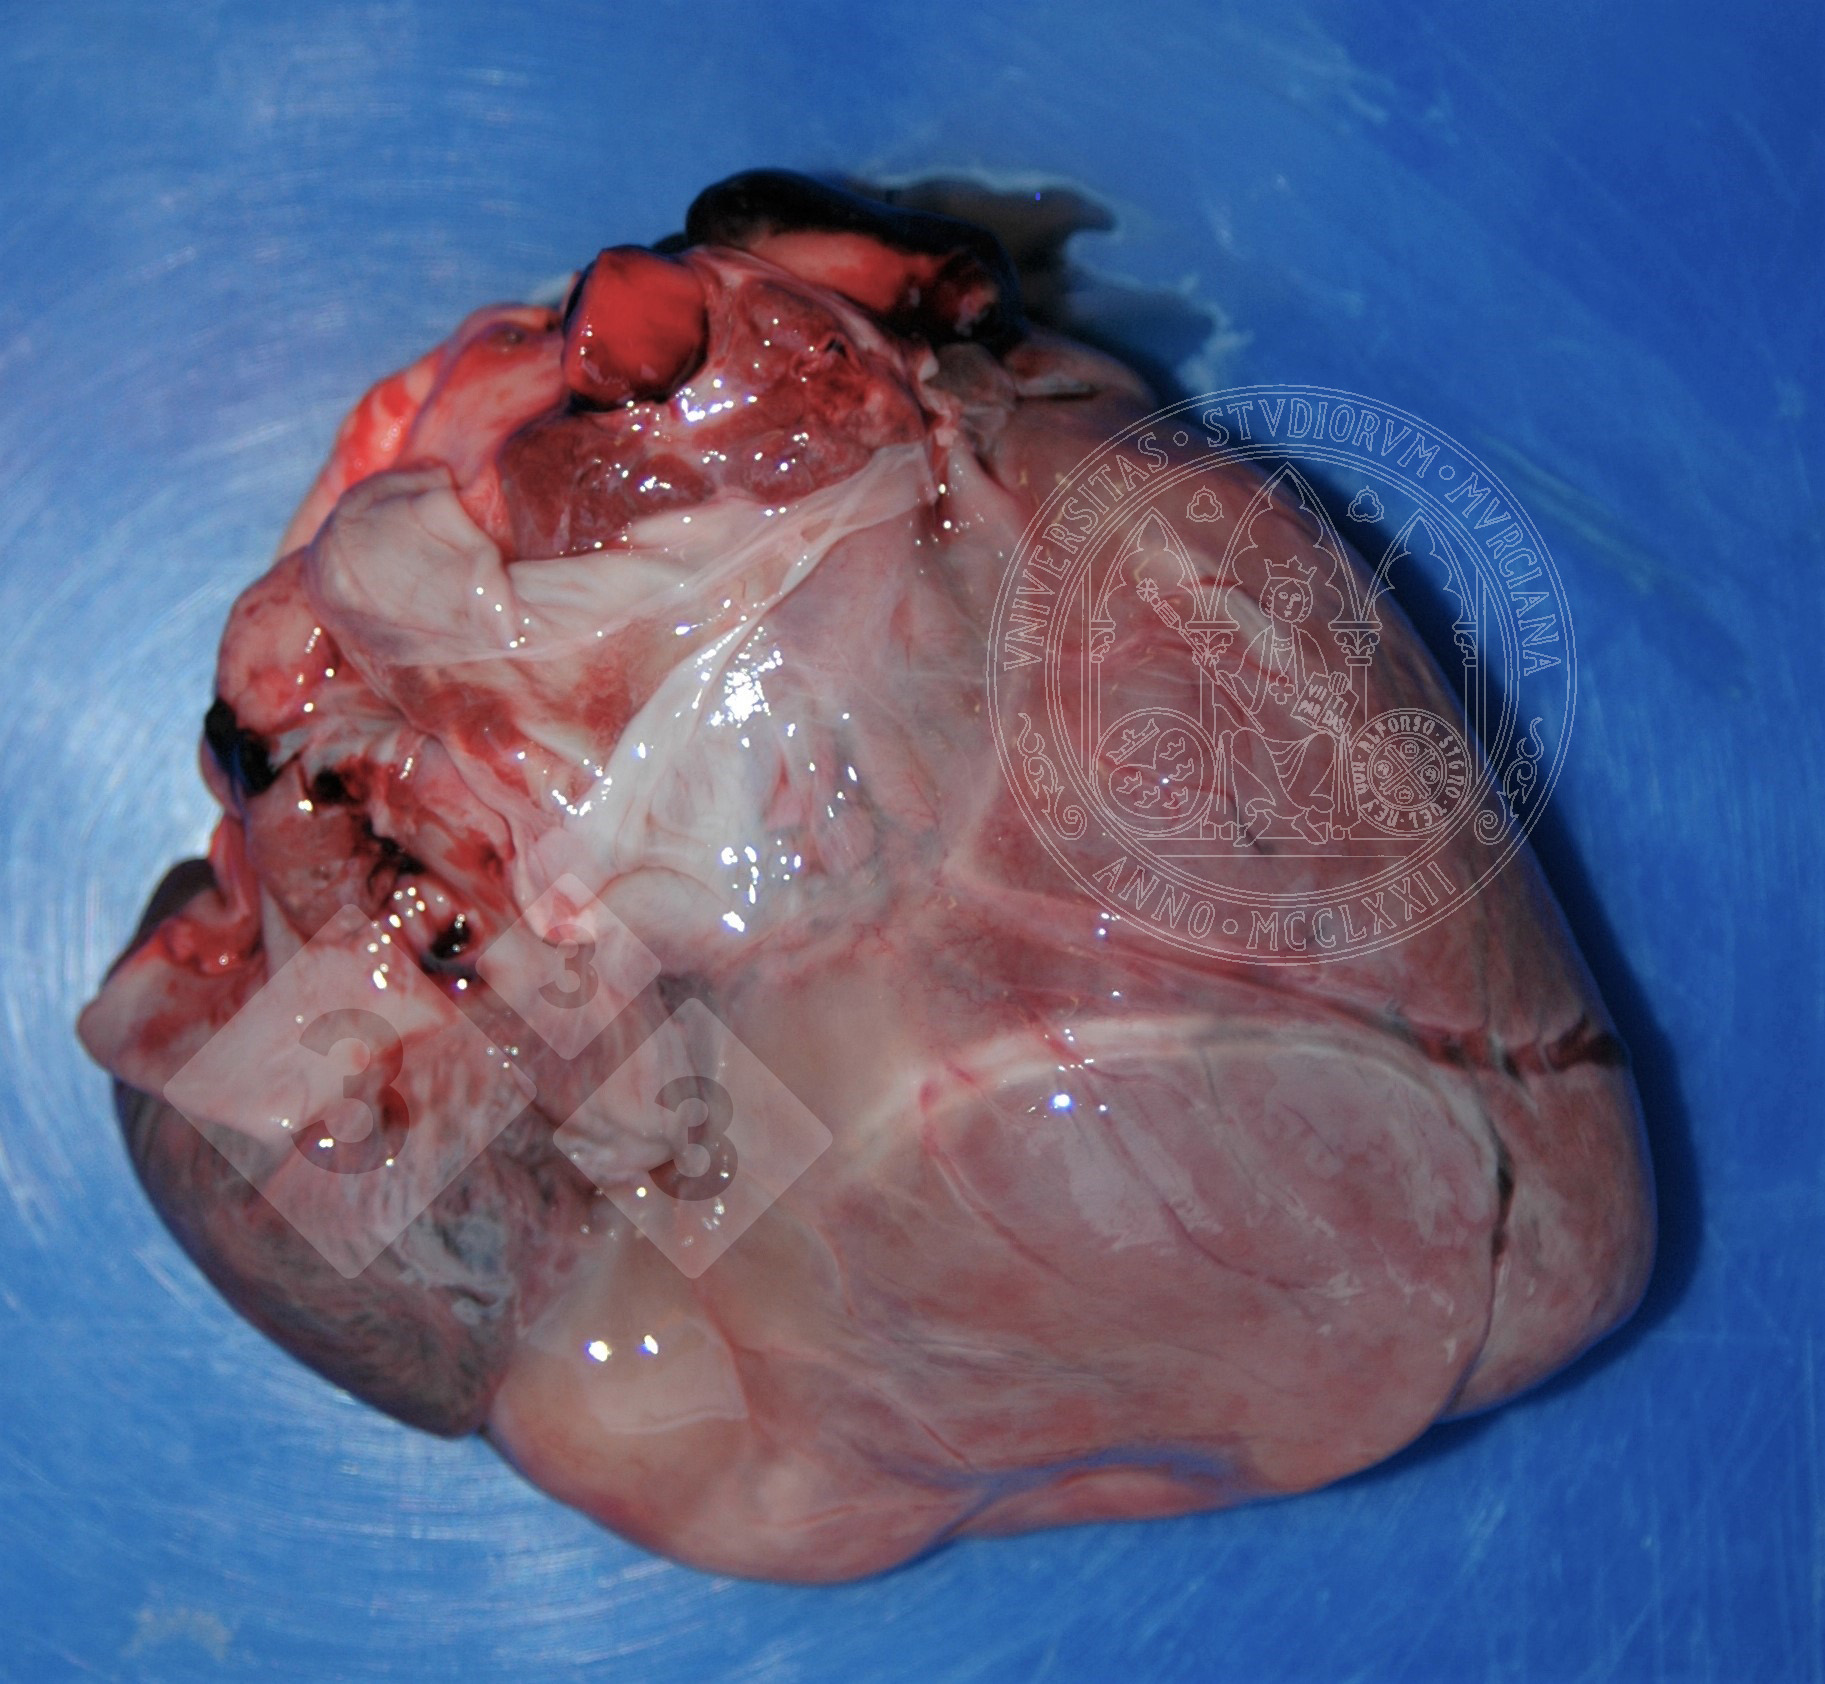

We can see this lesion in cases of cachexia. Due to several reasons, there can be a mobilization of the fat stores, such as that on the epicardium. The lipid vacuoles reduce their size and are replaced by a proteinaceous fluid, with a simultaneous increase in the interstitial fluid, developing a greyish gelatinous appearance. We can sometimes see small white fat necrosis spots.

We must make a differential diagnosis with oedema, whether with an infectious aetiology or not.